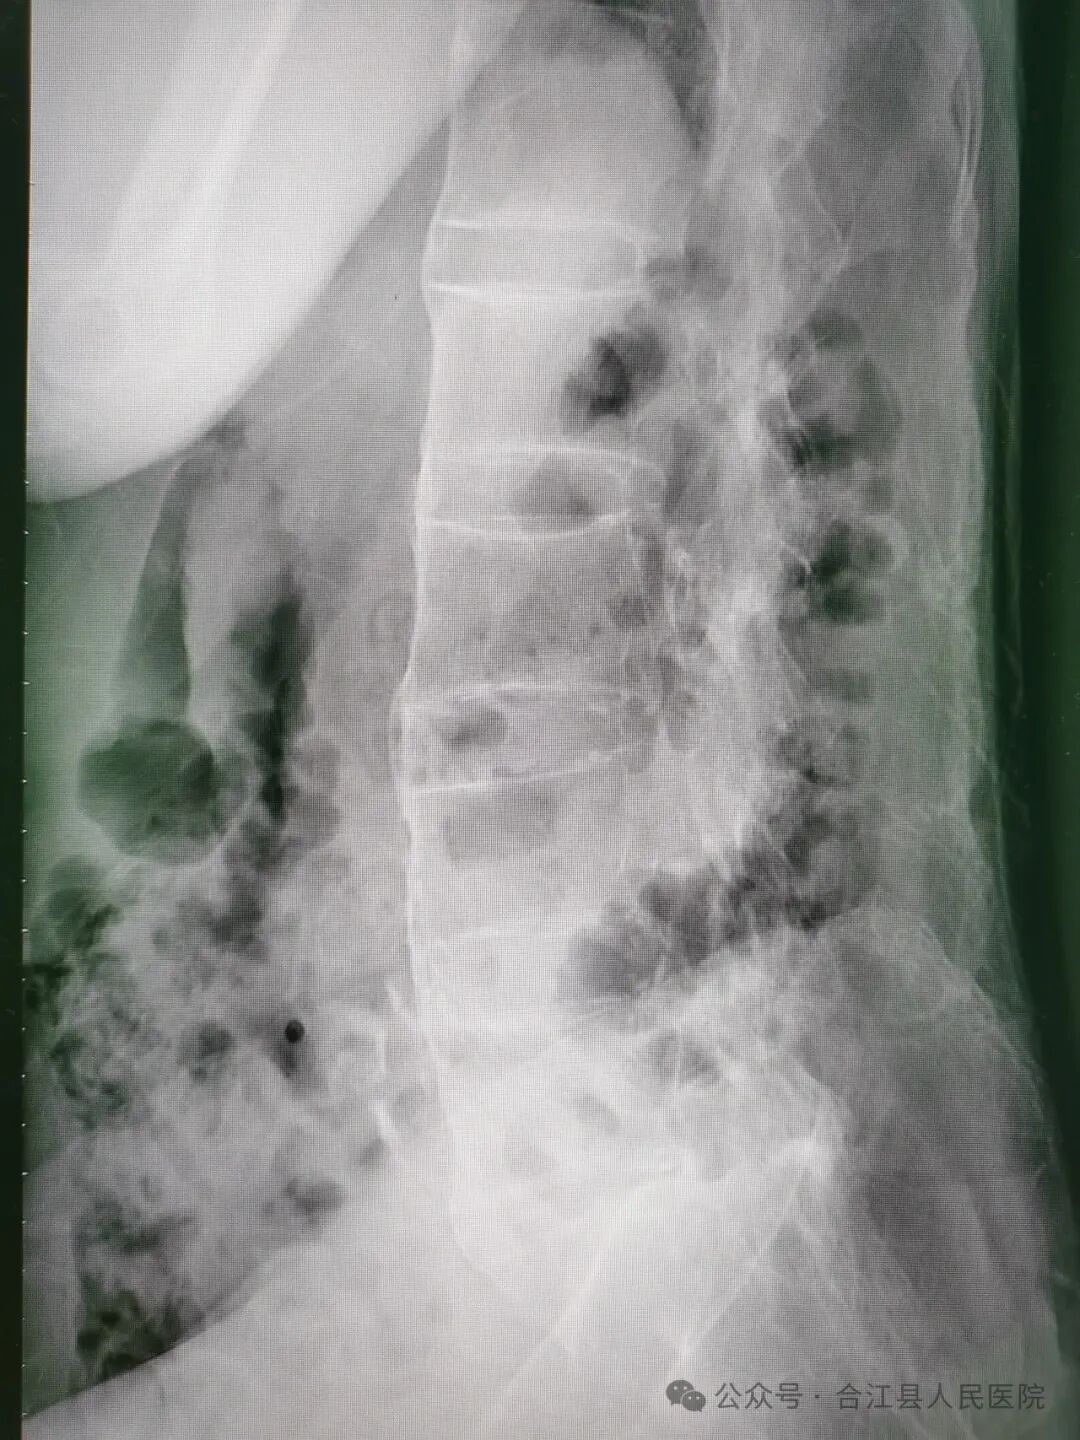

经创伤外科和麻醉科详细病史采集和查体,徐先生确实不是普通气道,气道处理非常棘手。颈椎、腰椎曲度变直,椎体“竹节样改变”。